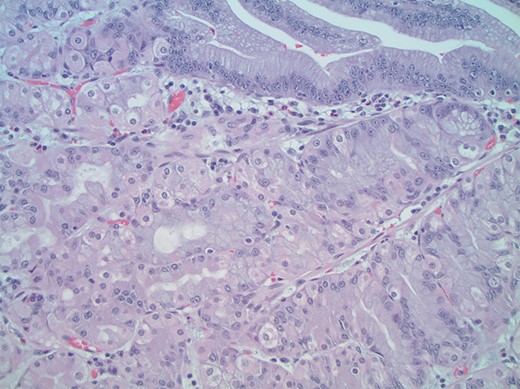

A 26-year-old woman with a history of omphalocele status post repair as a neonate presented to the emergency department (ED) for evaluation of recurrent severe abdominal pain. The abdominal pain was crampy, burning, periumbilical and associated with anorexia, bloating and constipation, mildly improved with induced vomiting. The patient experienced similar symptoms 1 year prior and underwent upper and lower endoscopy, gastric emptying study, and an abdominal ultrasound, all unremarkable. On presentation to the ED, her vital signs and laboratory results were all within normal limits. Conventional CT scan and CT enterography demonstrated a focally dilated segment of small bowel with normal afferent and efferent bowel on either side. Although imaging revealed no evidence of bowel obstruction or mass, diagnostic laparoscopy was performed due to her persistent symptoms. At laparoscopy, a 20 cm segment of abnormally dilated small bowel was identified in the mid ileum with a maximum width of 7 cm, bordered by normal-caliber small bowel (Fig. 1). The dilated segment was resected and an ileo-ileal anastomosis was performed. The resected segment was found to contain a 7 × 4.5 cm2 discrete island of abnormal appearing mucosa with rugal folding (Fig. 2). Histology revealed that this area consisted of heterotopic gastric glandular and foveolar epithelium with no abnormalities identified within the neuronal plexus proximal or distal to this mass (Figs 3 and 4). The patient had an uneventful recovery and was discharged home on postoperative day three. At 6-month follow-up, she reported no recurrence of her symptoms.

High-power magnification (×400) views of the mass show a mixture of gastric foveolar (top right) and fundic glandular epithelium including parietal and chief cells consistent with true gastric heterotopia.